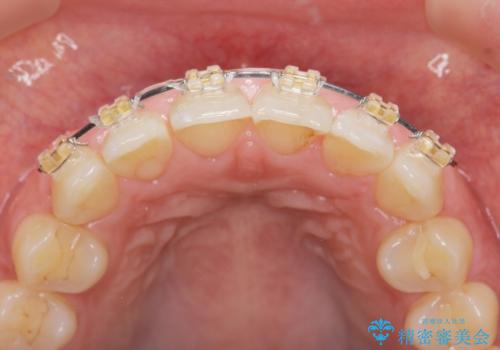

前歯のガタつきをきれいに マウスピース矯正治療

- 「前歯のガタつきをきれいにしたい。」と矯正治療を希望され来院されました。

前歯のガタつきをワイヤー部分矯正、上顎前突の咬合関係を後方移動することで理想的な咬合関係を確立します。

上顎の全体的な後方移動を実現するためにマイクロインプラントを併用したゴムかけを行ったことで理想的な咬合関係を確立することができました。